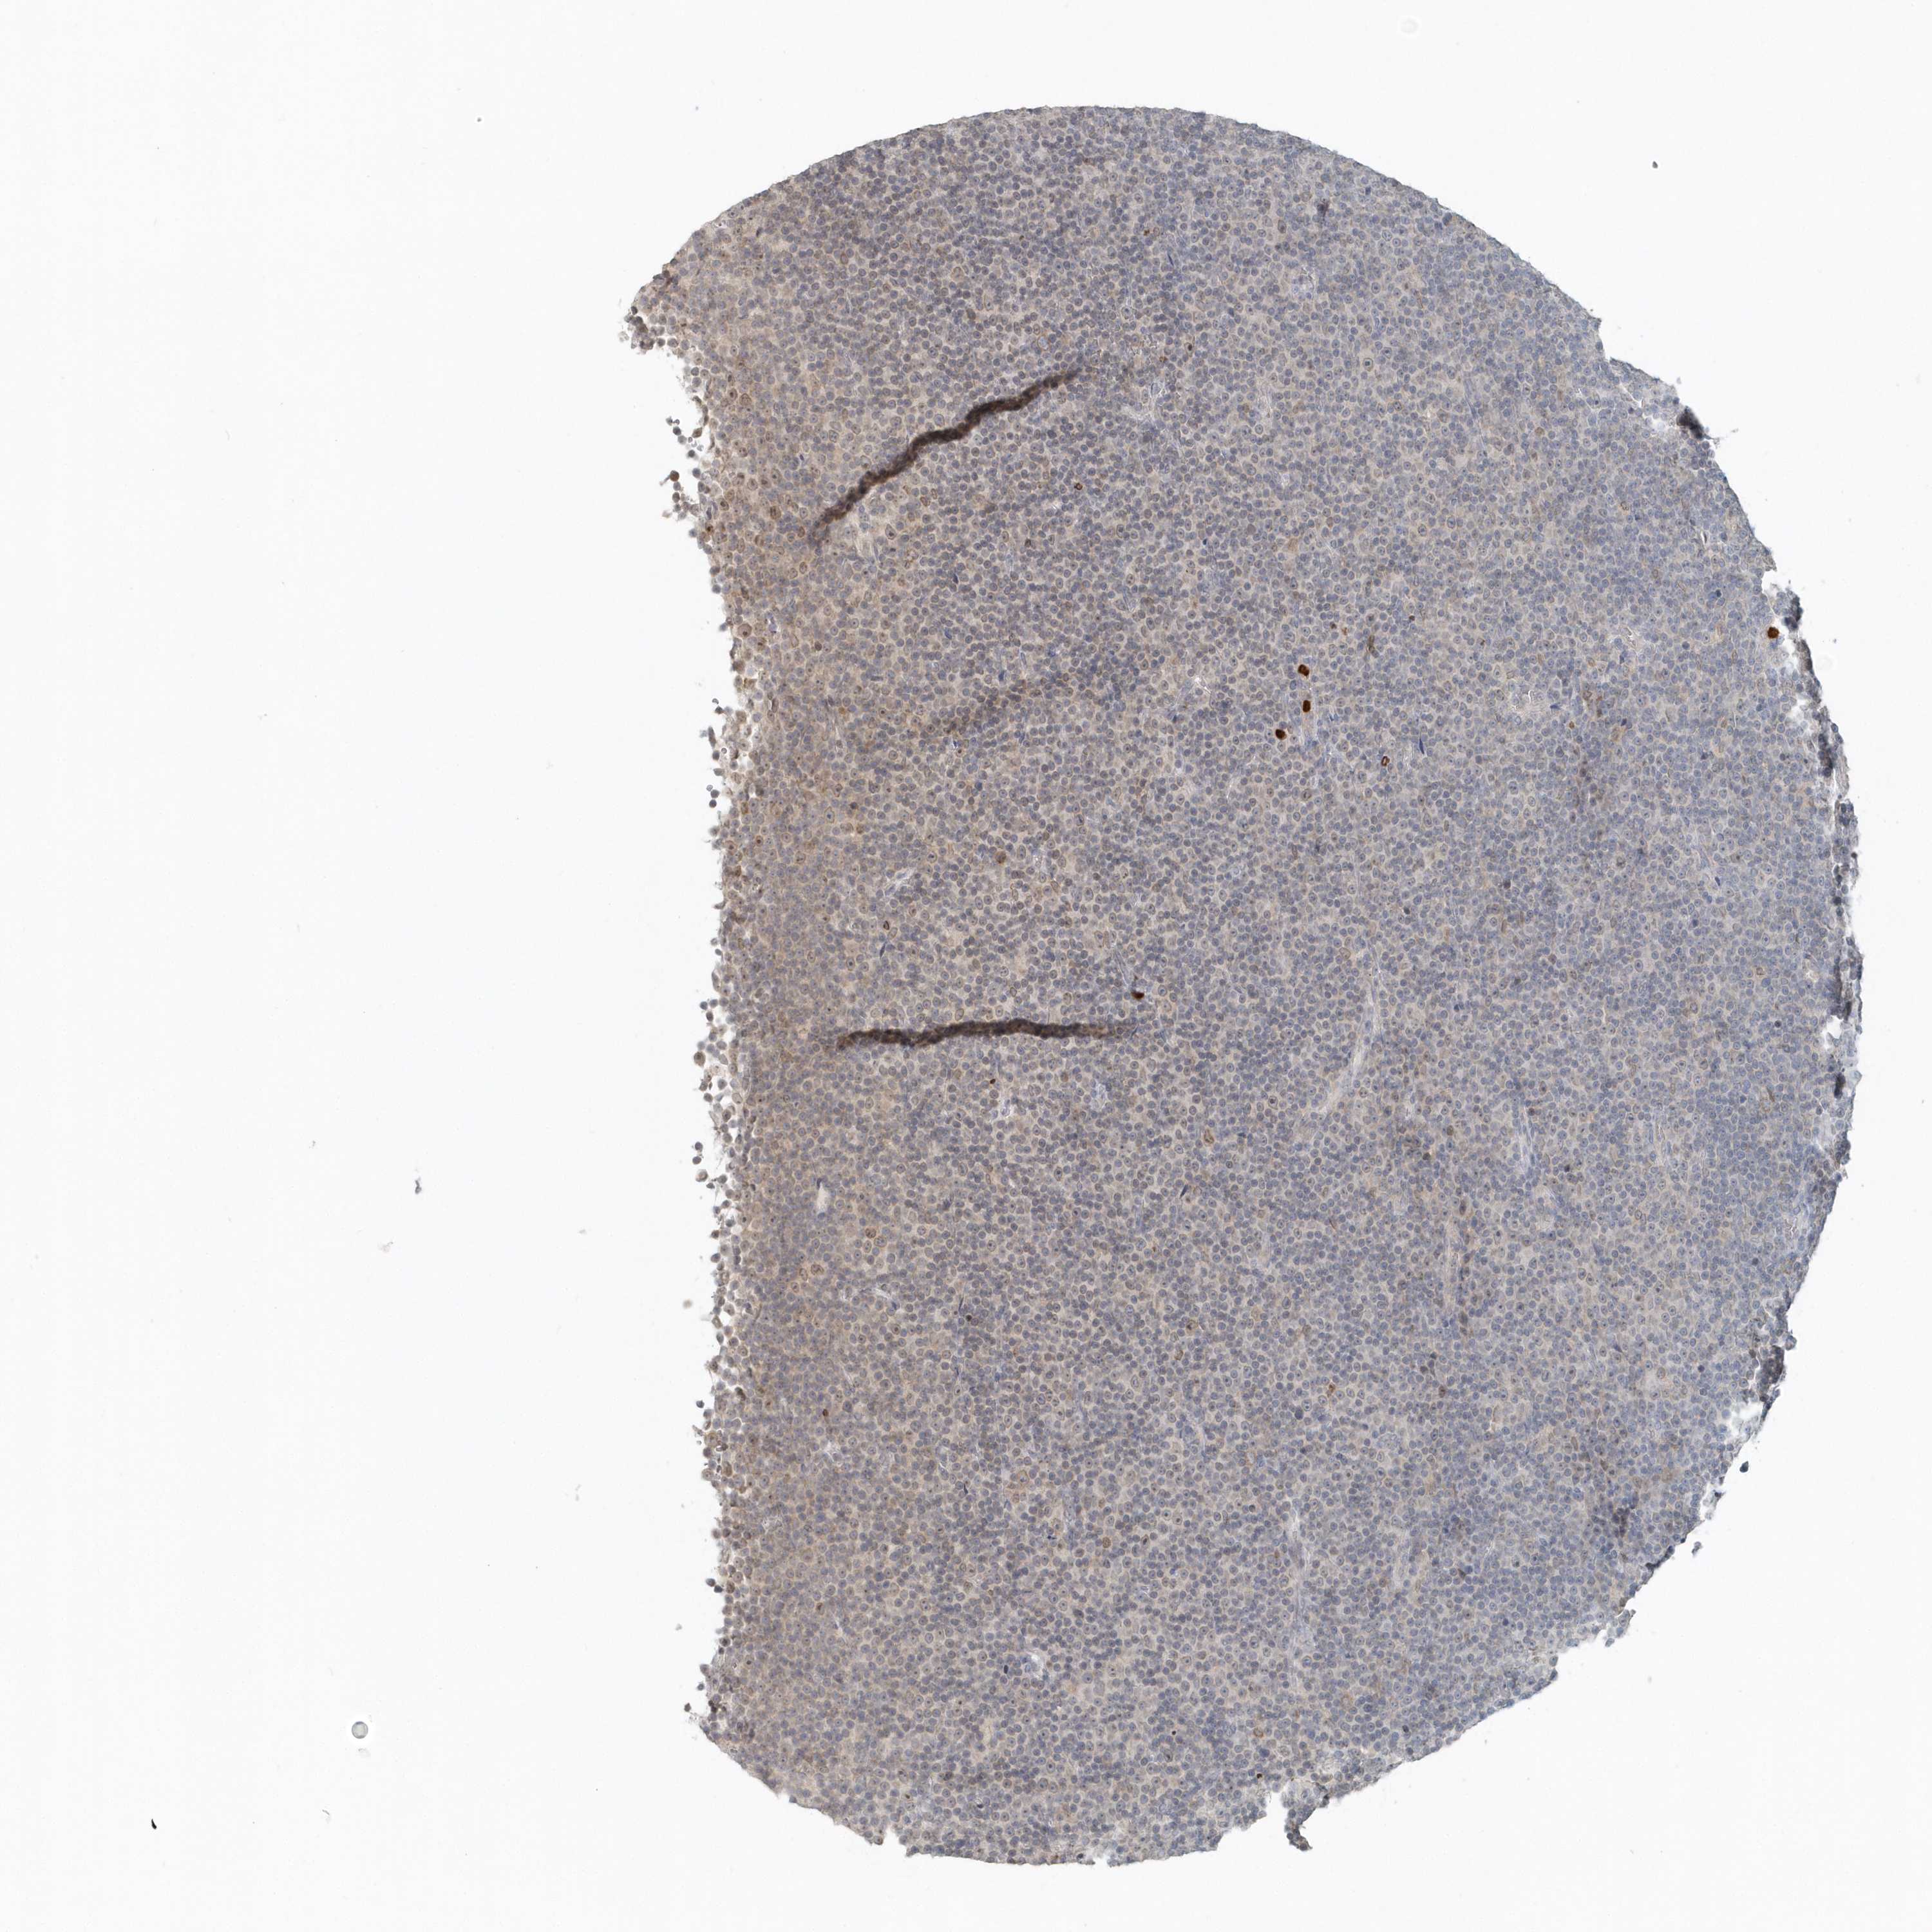

LYMPHOMA - Protein expressioni

A mouse-over function shows sample information and annotation data. Click on an image to view it in a full screen mode. Samples can be filtered based on level of antibody staining by selecting one or several of the following categories: high, medium, low and not detected. The assay and annotation is described here.

Antibody stainingi

Antibody staining in the annotated cell types in the current human tissue is reported as not detected, low, medium, or high, based on conventional immunohistochemistry profiling in selected tissues. This score is based on the combination of the staining intensity and fraction of stained cells.

Each image is clickable and will lead to virtual microscopy that enables deeper exploration of all samples and also displays staining intensity scores, fraction scores and subcellular localization as well as patient and tissue information for each sample.

Antibody HPA035929

Hodgkin's disease, NOS

Malignant lymphoma, non-Hodgkin's type, High grade

Malignant lymphoma, non-Hodgkin's type, Low grade